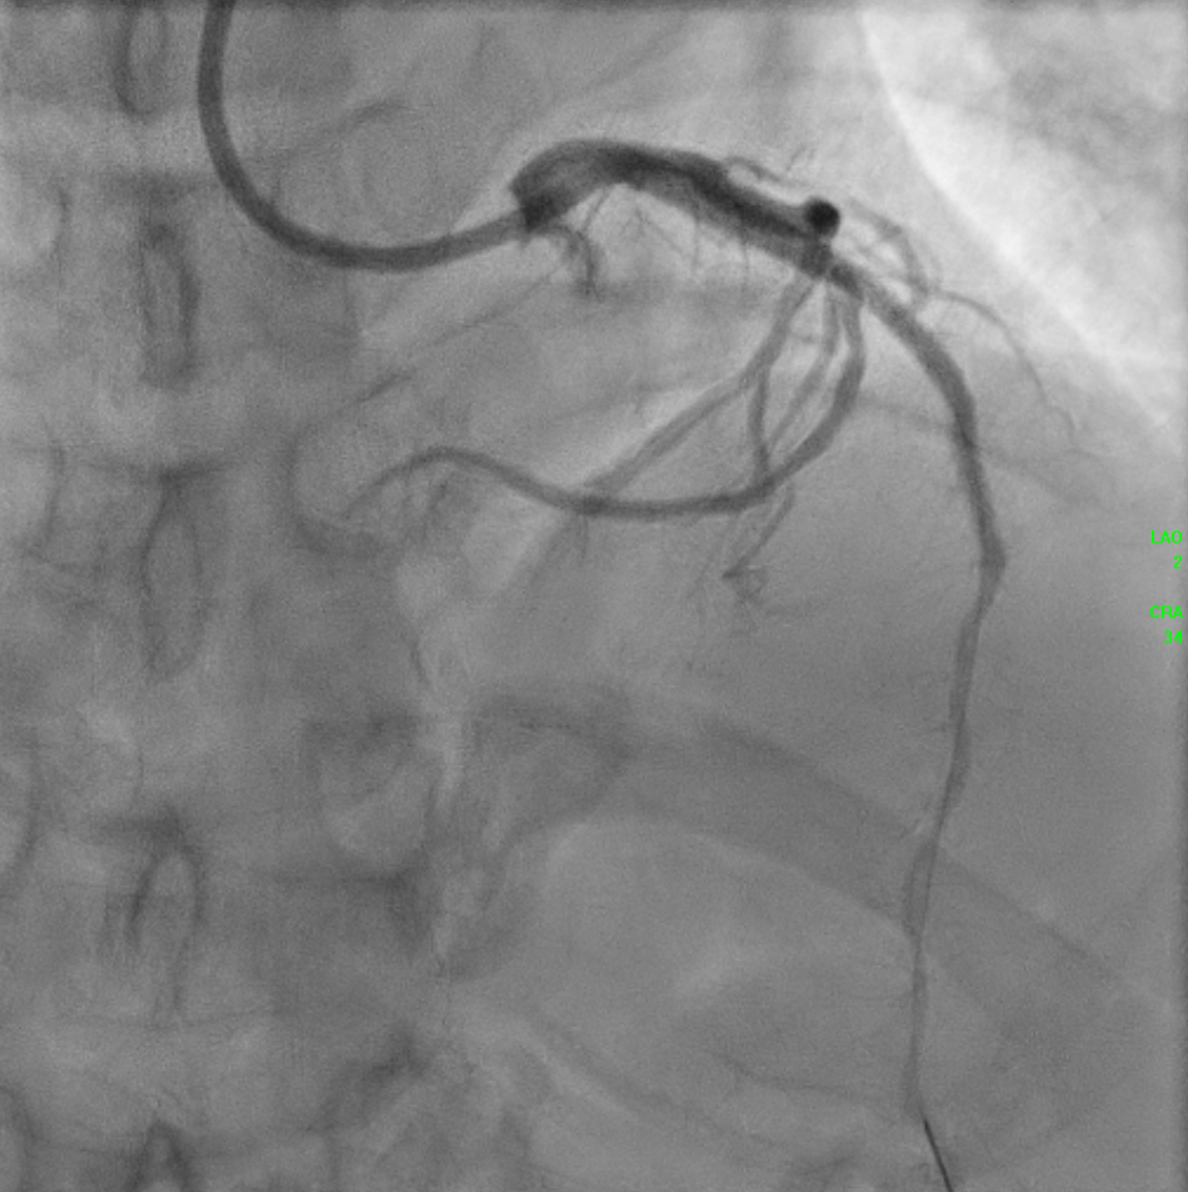

An IVUS-guided PCI of the LAD and RCA was performed via right radial access. An EBU 3.5, 7 Fr guiding catheter engaged the left main, and a Sion Blue wire was advanced to the distal LAD for pre-dilatation with a 2.5 mm NC balloon. Wiring the anomalous RCA from the LAD was challenging due to a retroflexed ostium but was achieved using a reverse wire technique with adual-lumen (Sasuke) catheter and Sion Black wire. Difficulty crossing the mid RCA, likely due to dissection, required multiple wire exchanges before reaching the distal RCA. Lesion preparation used 2.0 mm and 1.5 mm NC balloons in the RCA. IVUS showed LAD diameters of 2.5mm distally with diffuse disease and < 40%plaque burden. A hybrid revascularization strategy was planned. Further preparation involved 3.0 mm and 2.0 mm balloons in the LAD and RCA. DCBs (2.0 ¡¿25 mm in distal LAD; 2.0 ¡¿ 20 mm in RCA) were applied for 60 seconds each. A Xience Sierra 3.0 ¡¿ 38 mm DES was deployed in the proximal–mid LAD,post-dilated with 3.0–3.5 mm NC balloons and optimized with a 4.0 mm POT. IVUS revealed a distal edge dissection, covered with an additional overlapping Xience Sierra 2.75 ¡¿ 23 mm DES. Final IVUS confirmed good stent expansion (MSA6 mm©÷), and angiography showed non–flow-limiting distal LAD dissection with TIMI 3 flow in both LAD and RCA.

21 Final Angio.mp4